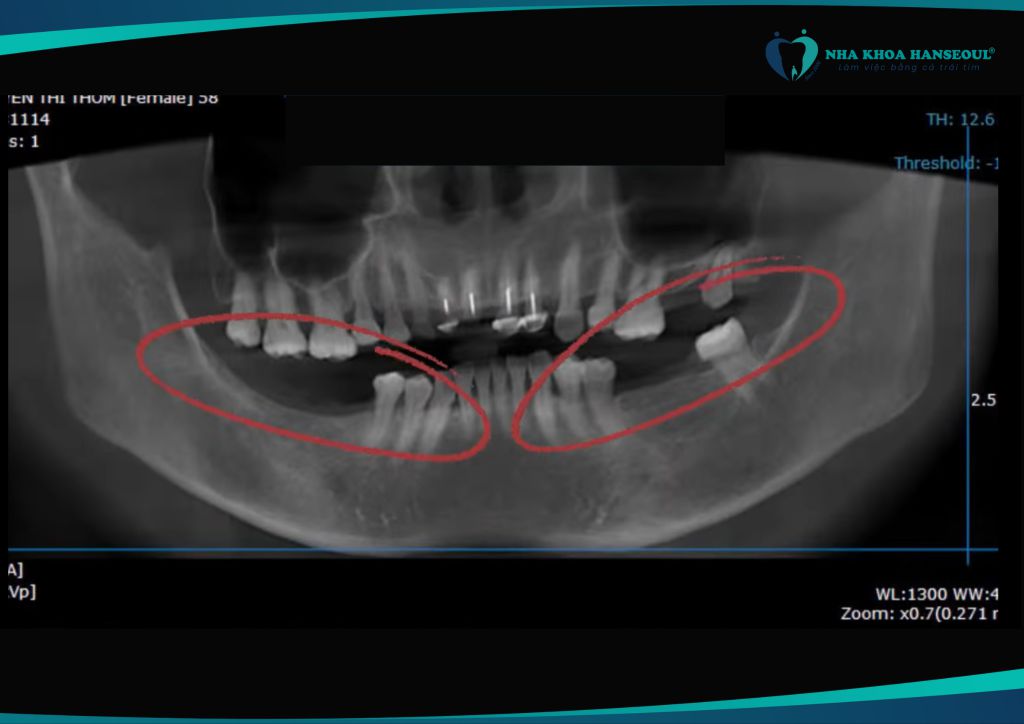

Cô Nguyễn Thị Thơm, sinh năm 1964, đến với Nha khoa Hanseoul trong tình trạng mất nhiều răng. Trong đó bao gồm cả những răng hàm có chức năng ăn nhai chủ lực. Kèm theo 3 răng có dấu hiệu sa xuống. Hậu quả là cô thường phải nhai bằng lợi. Điều này không chỉ gây đau đớn mỗi lần ăn mà còn khiến cô không thể thưởng thức các món ăn cứng hoặc dai.

Sau khi được bác sĩ chuyên môn thăm khám và tư vấn, cô Thơm được chỉ định cấy ghép răng Implant với công nghệ Hansafe. Đây là công nghệ định vị trụ tiên tiến được ứng dụng độc quyền tại Hanseoul.